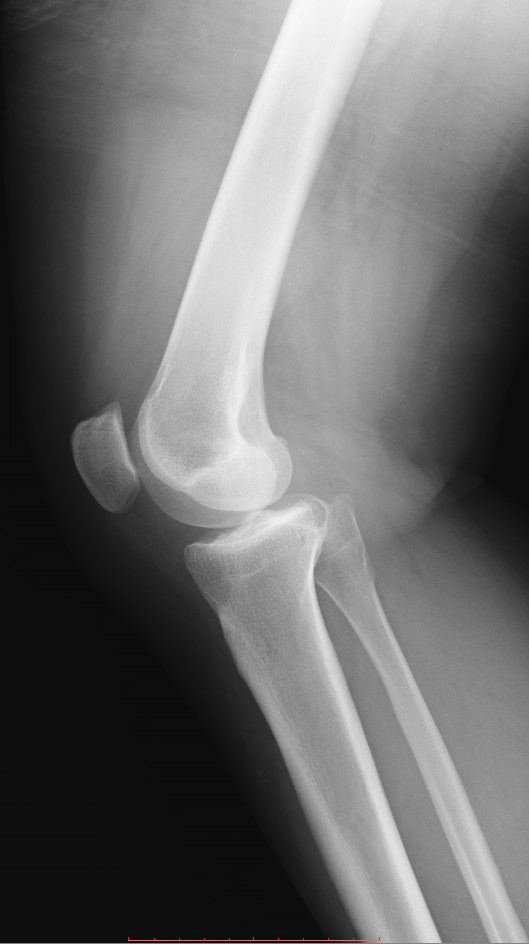

Женщина 1982 года, боль в правом коленном суставе в течении 2 лет, периодически лечит (подкалывает в сустав что-то, не помнит препарат).

Не нравится латеральный мыщелок правой бедренной кости, интересует ваше мнение коллеги?

Мыщелок как мыщелок. Артроз как артроз (без стадии!, коллеги). Отметил бы выраженную дисконгруэнтность суставных поверхностей.

На мой взгляд, есть некоторая гипоплазия латеральных мыщелков бедренных костей. Кажется, собственного названия она не имеет, но в целом может быть предрасполагающим фактором.

Судя по медиальным щелям - повреждены медиальные мениски.